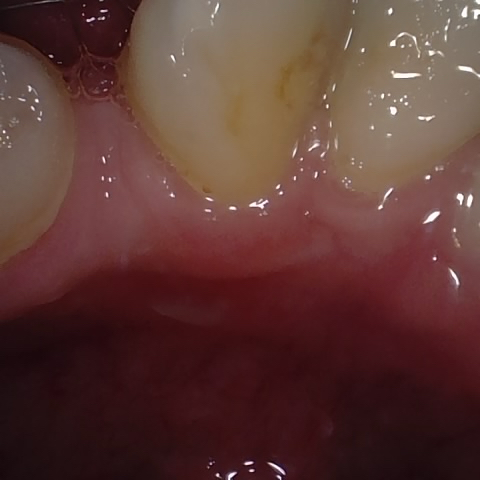

NHD20794

Annotated as "Bad"